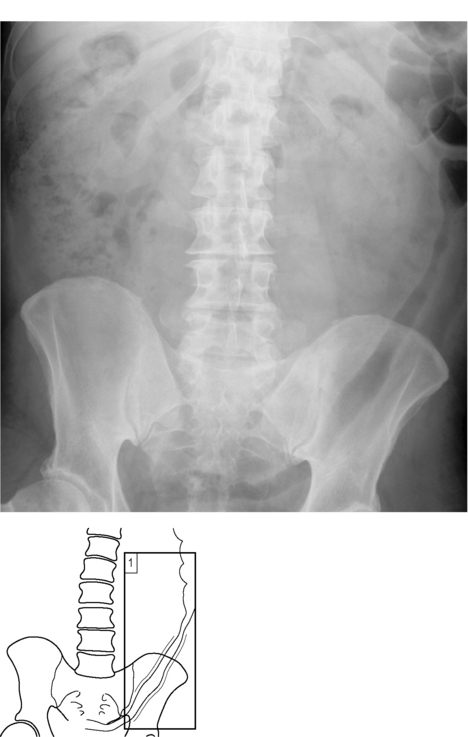

Crohns Disease Xray

Crohn's disease | Radiology Case | Radiopaedia.org Crohn's Disease Radiology: CT, MRI, Ultrasound, and More LearningRadiology - Crohn Disease, Regional Enteritis Crohn disease - X-ray: MedlinePlus Medical Encyclopedia Image | Crohns Disease Xray